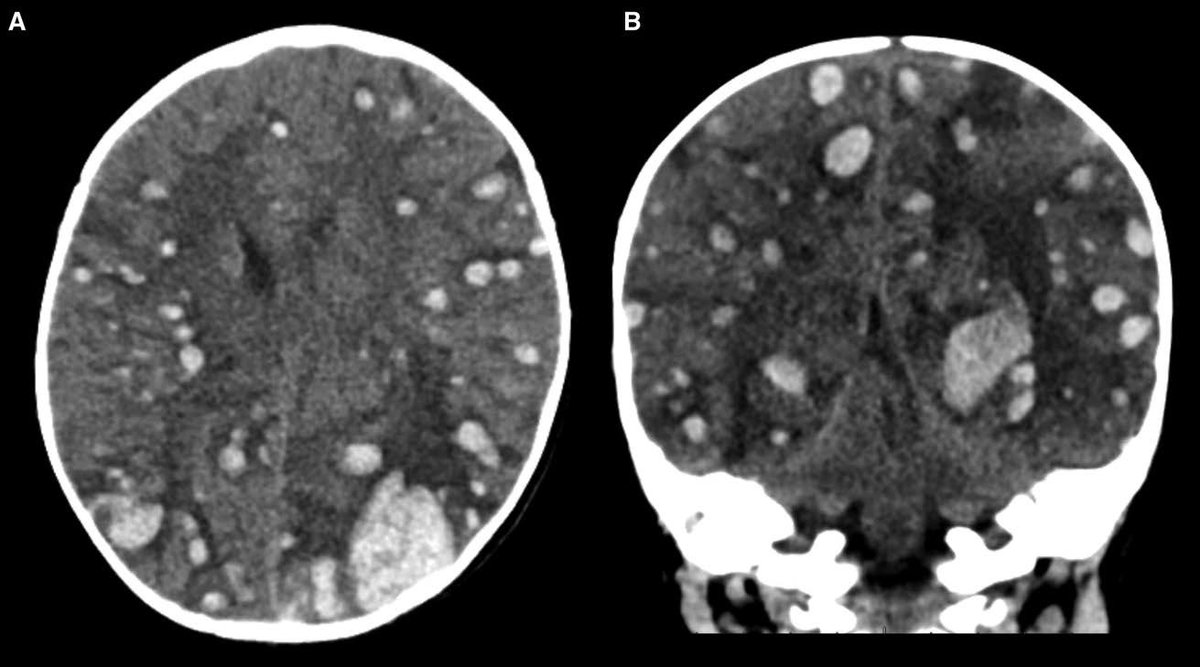

#STROKE Images: Chemotherapy, thrombocytopenia, disseminated intravascular coagulation and sepsis can trigger sudden, multi-focal intracerebral hemorrhage in the setting of leukemia. @AlexRebchuk @UBCmedicine #AHAJournals https://t.co/7Pj2FkjV3m

Just published an interesting case report in @StrokeAHA_ASA of a polka dot ICH pattern https://t.co/VTl9C8GWv3